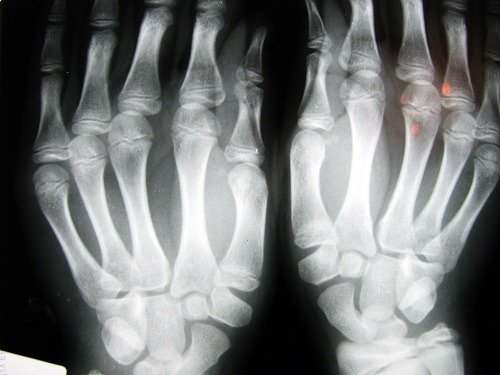

Knogleskørhed er en knoglesygdom, der forårsager et fald i massefylden af knoglemassen. Denne sygdom er kendetegnet ved porøse knogler. Ved at øge størrelsen af de indre celler i knoglerne bliver de skøre og brækkere lettere.

Denne sygdom er tavs, fordi den ofte går ubemærket, indtil den allerede har forårsaget lidt skade på knoglen.

Frakturer forekommer ofte i håndledene, og også i hofternes hvirvler. Dette er det mest alvorlige brud, fordi det indebærer øjeblikkelig kirurgisk indgreb og alvorlige konsekvenser for patientens helbred.